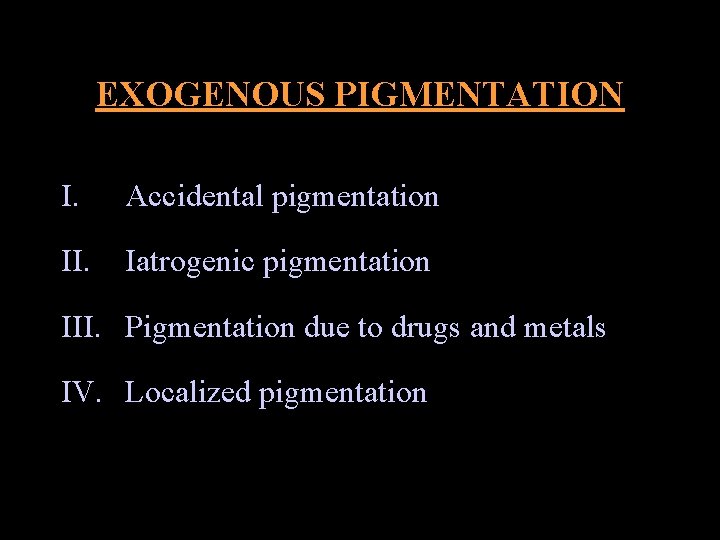

EXOGENOUS PIGMENTATION I. Accidental pigmentation II. Iatrogenic pigmentation III. Pigmentation due to drugs and metals IV. Localized pigmentation